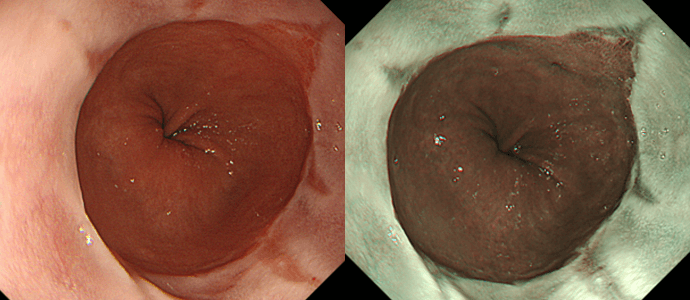

逆流性食道炎(右はNBI観察像)逆流性食道炎(右はNBI観察像)